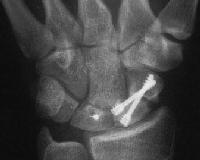

With intercalated iliac bone graft...

Click for larger image